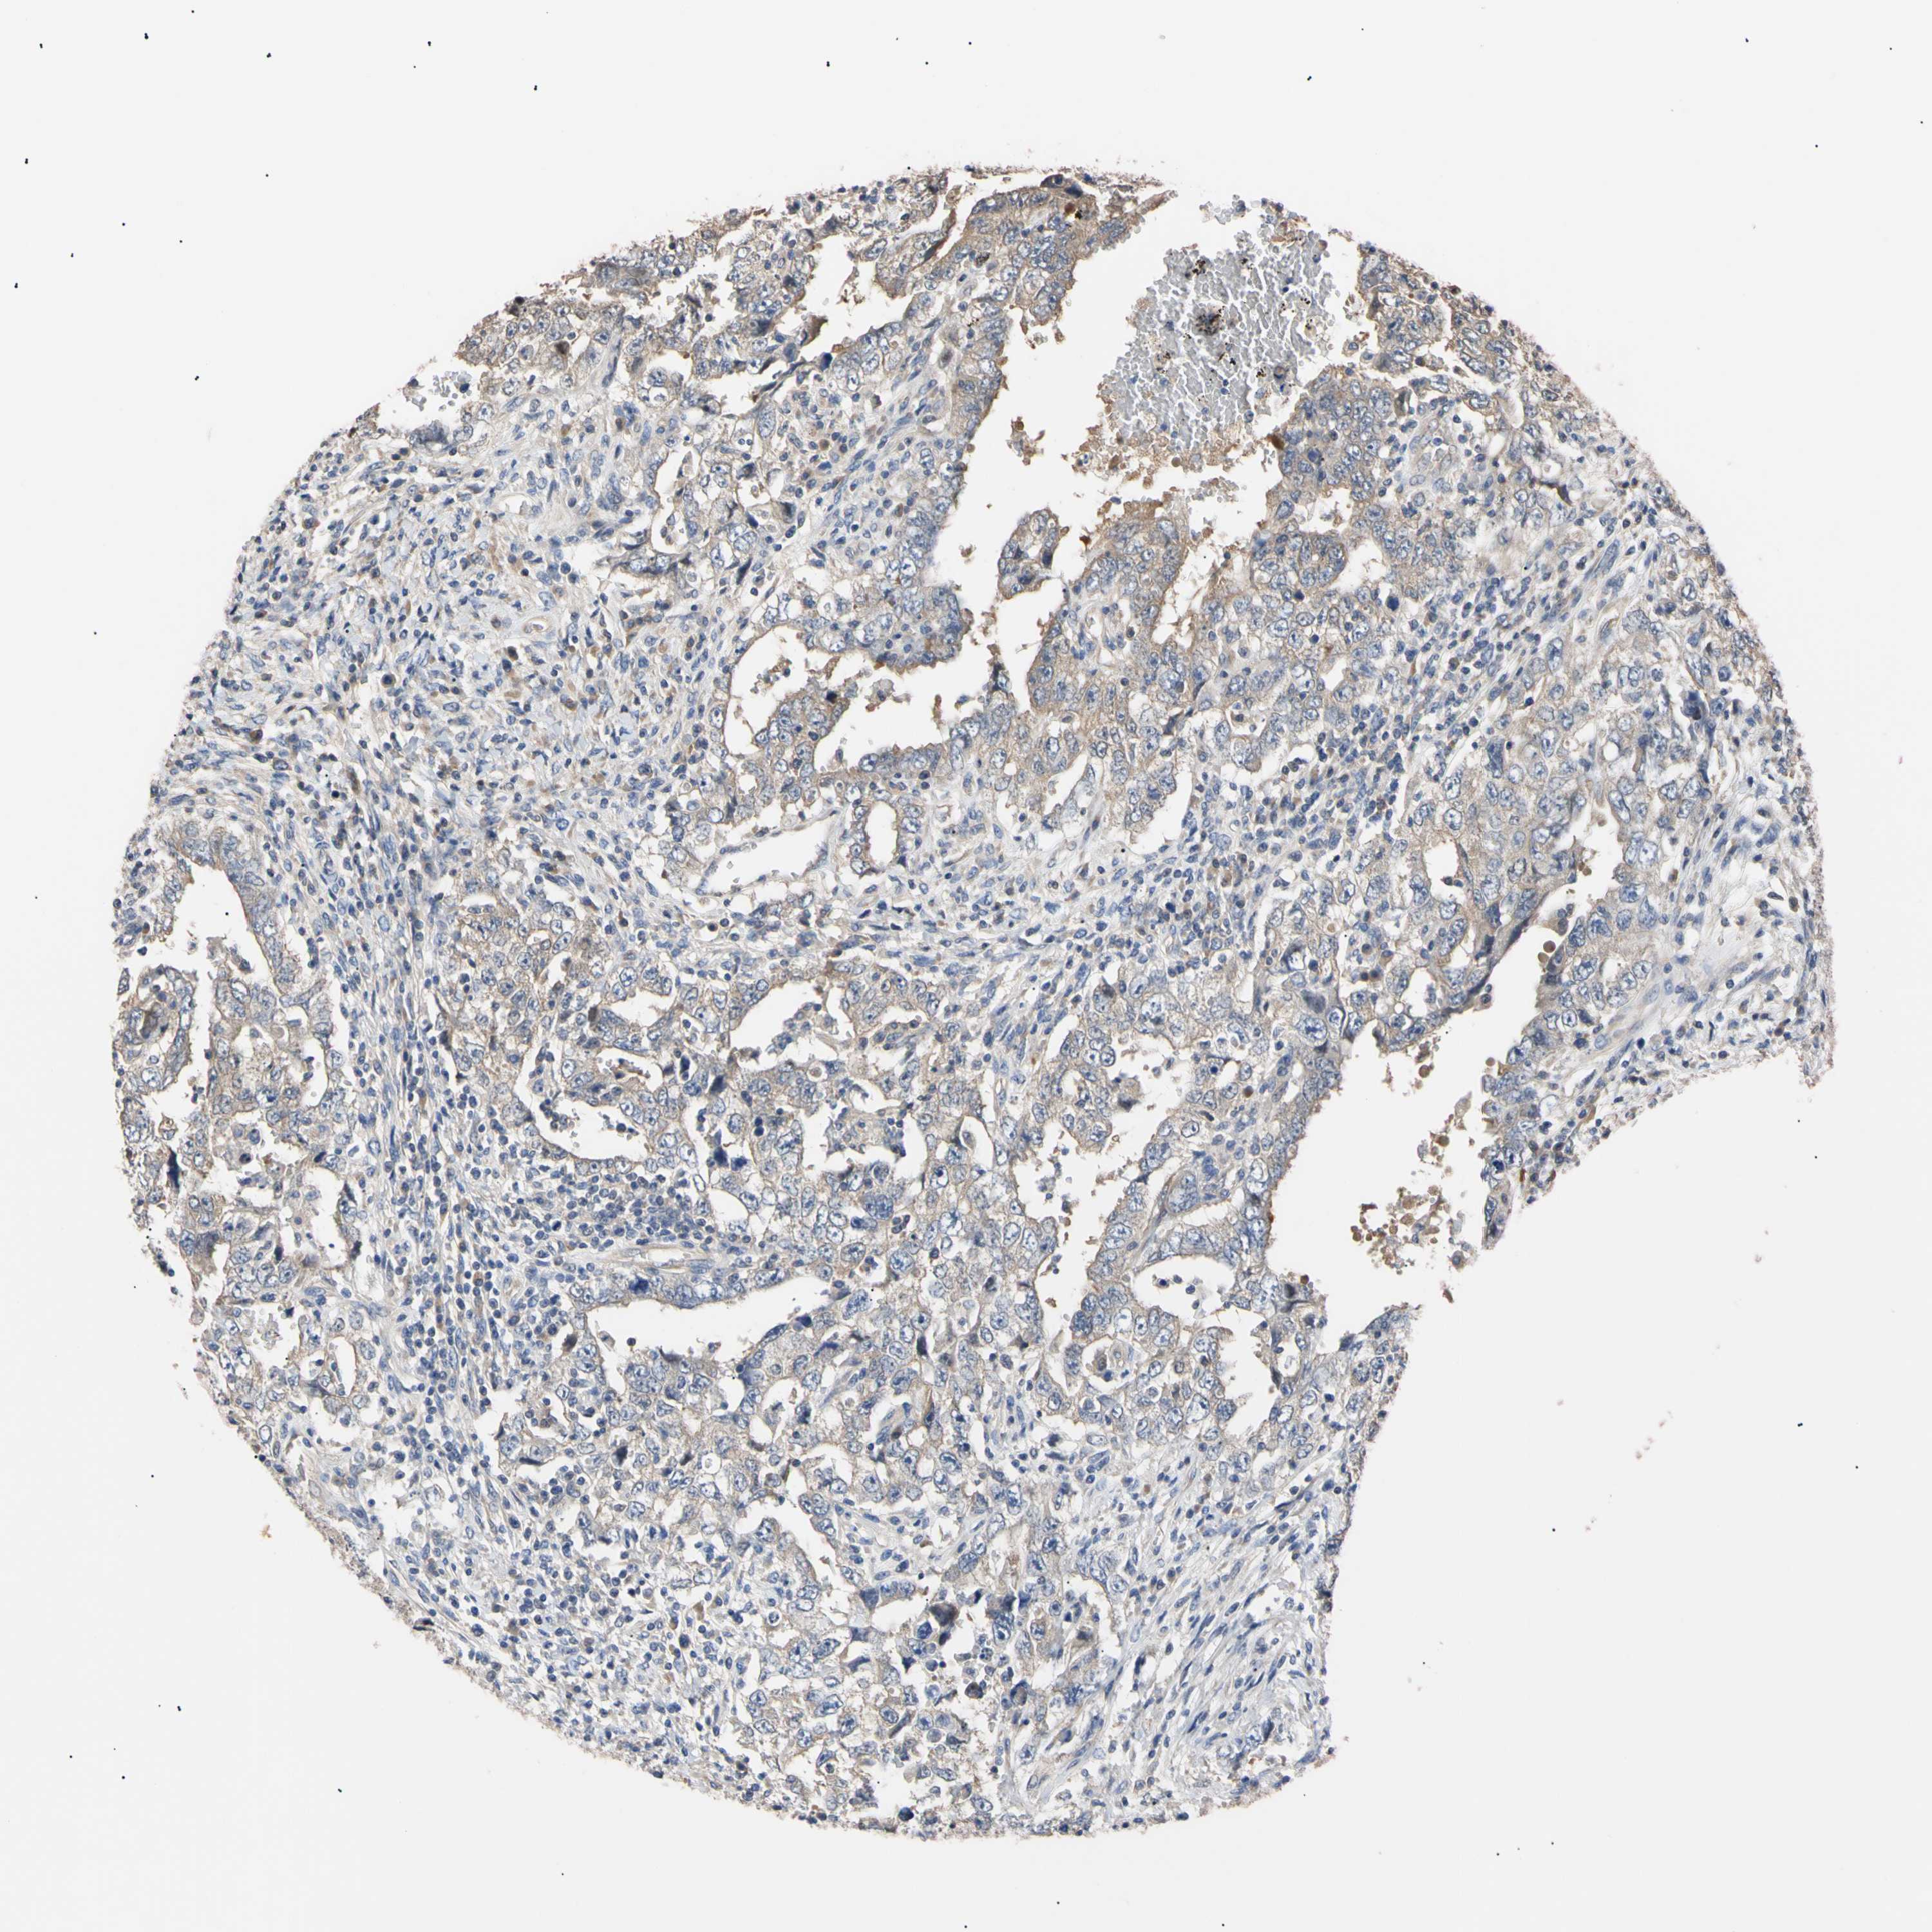

TESTIS CANCER - Protein expressioni

A mouse-over function shows sample information and annotation data. Click on an image to view it in a full screen mode. Samples can be filtered based on level of antibody staining by selecting one or several of the following categories: high, medium, low and not detected. The assay and annotation is described here.

Note that samples used for immunohistochemistry by the Human Protein Atlas do not correspond to samples in the TCGA dataset.

Antibody stainingi

Antibody staining in the annotated cell types in the current human tissue is reported as not detected, low, medium, or high, based on conventional immunohistochemistry profiling in selected tissues. This score is based on the combination of the staining intensity and fraction of stained cells.

Each image is clickable and will lead to virtual microscopy that enables deeper exploration of all samples and also displays staining intensity scores, fraction scores and subcellular localization as well as patient and tissue information for each sample.

Antibody HPA003979

Antibody HPA004130

Staining

High

Medium

Low

Not detected

Intensity

Strong

Moderate

Weak

Negative

Quantity

>75%

75%-25%

<25%

None

Location

Nuclear

Cytoplasmic/membranous

Cytoplasmic/membranous,nuclear

Carcinoma, Embryonal, NOS

Seminoma, NOS